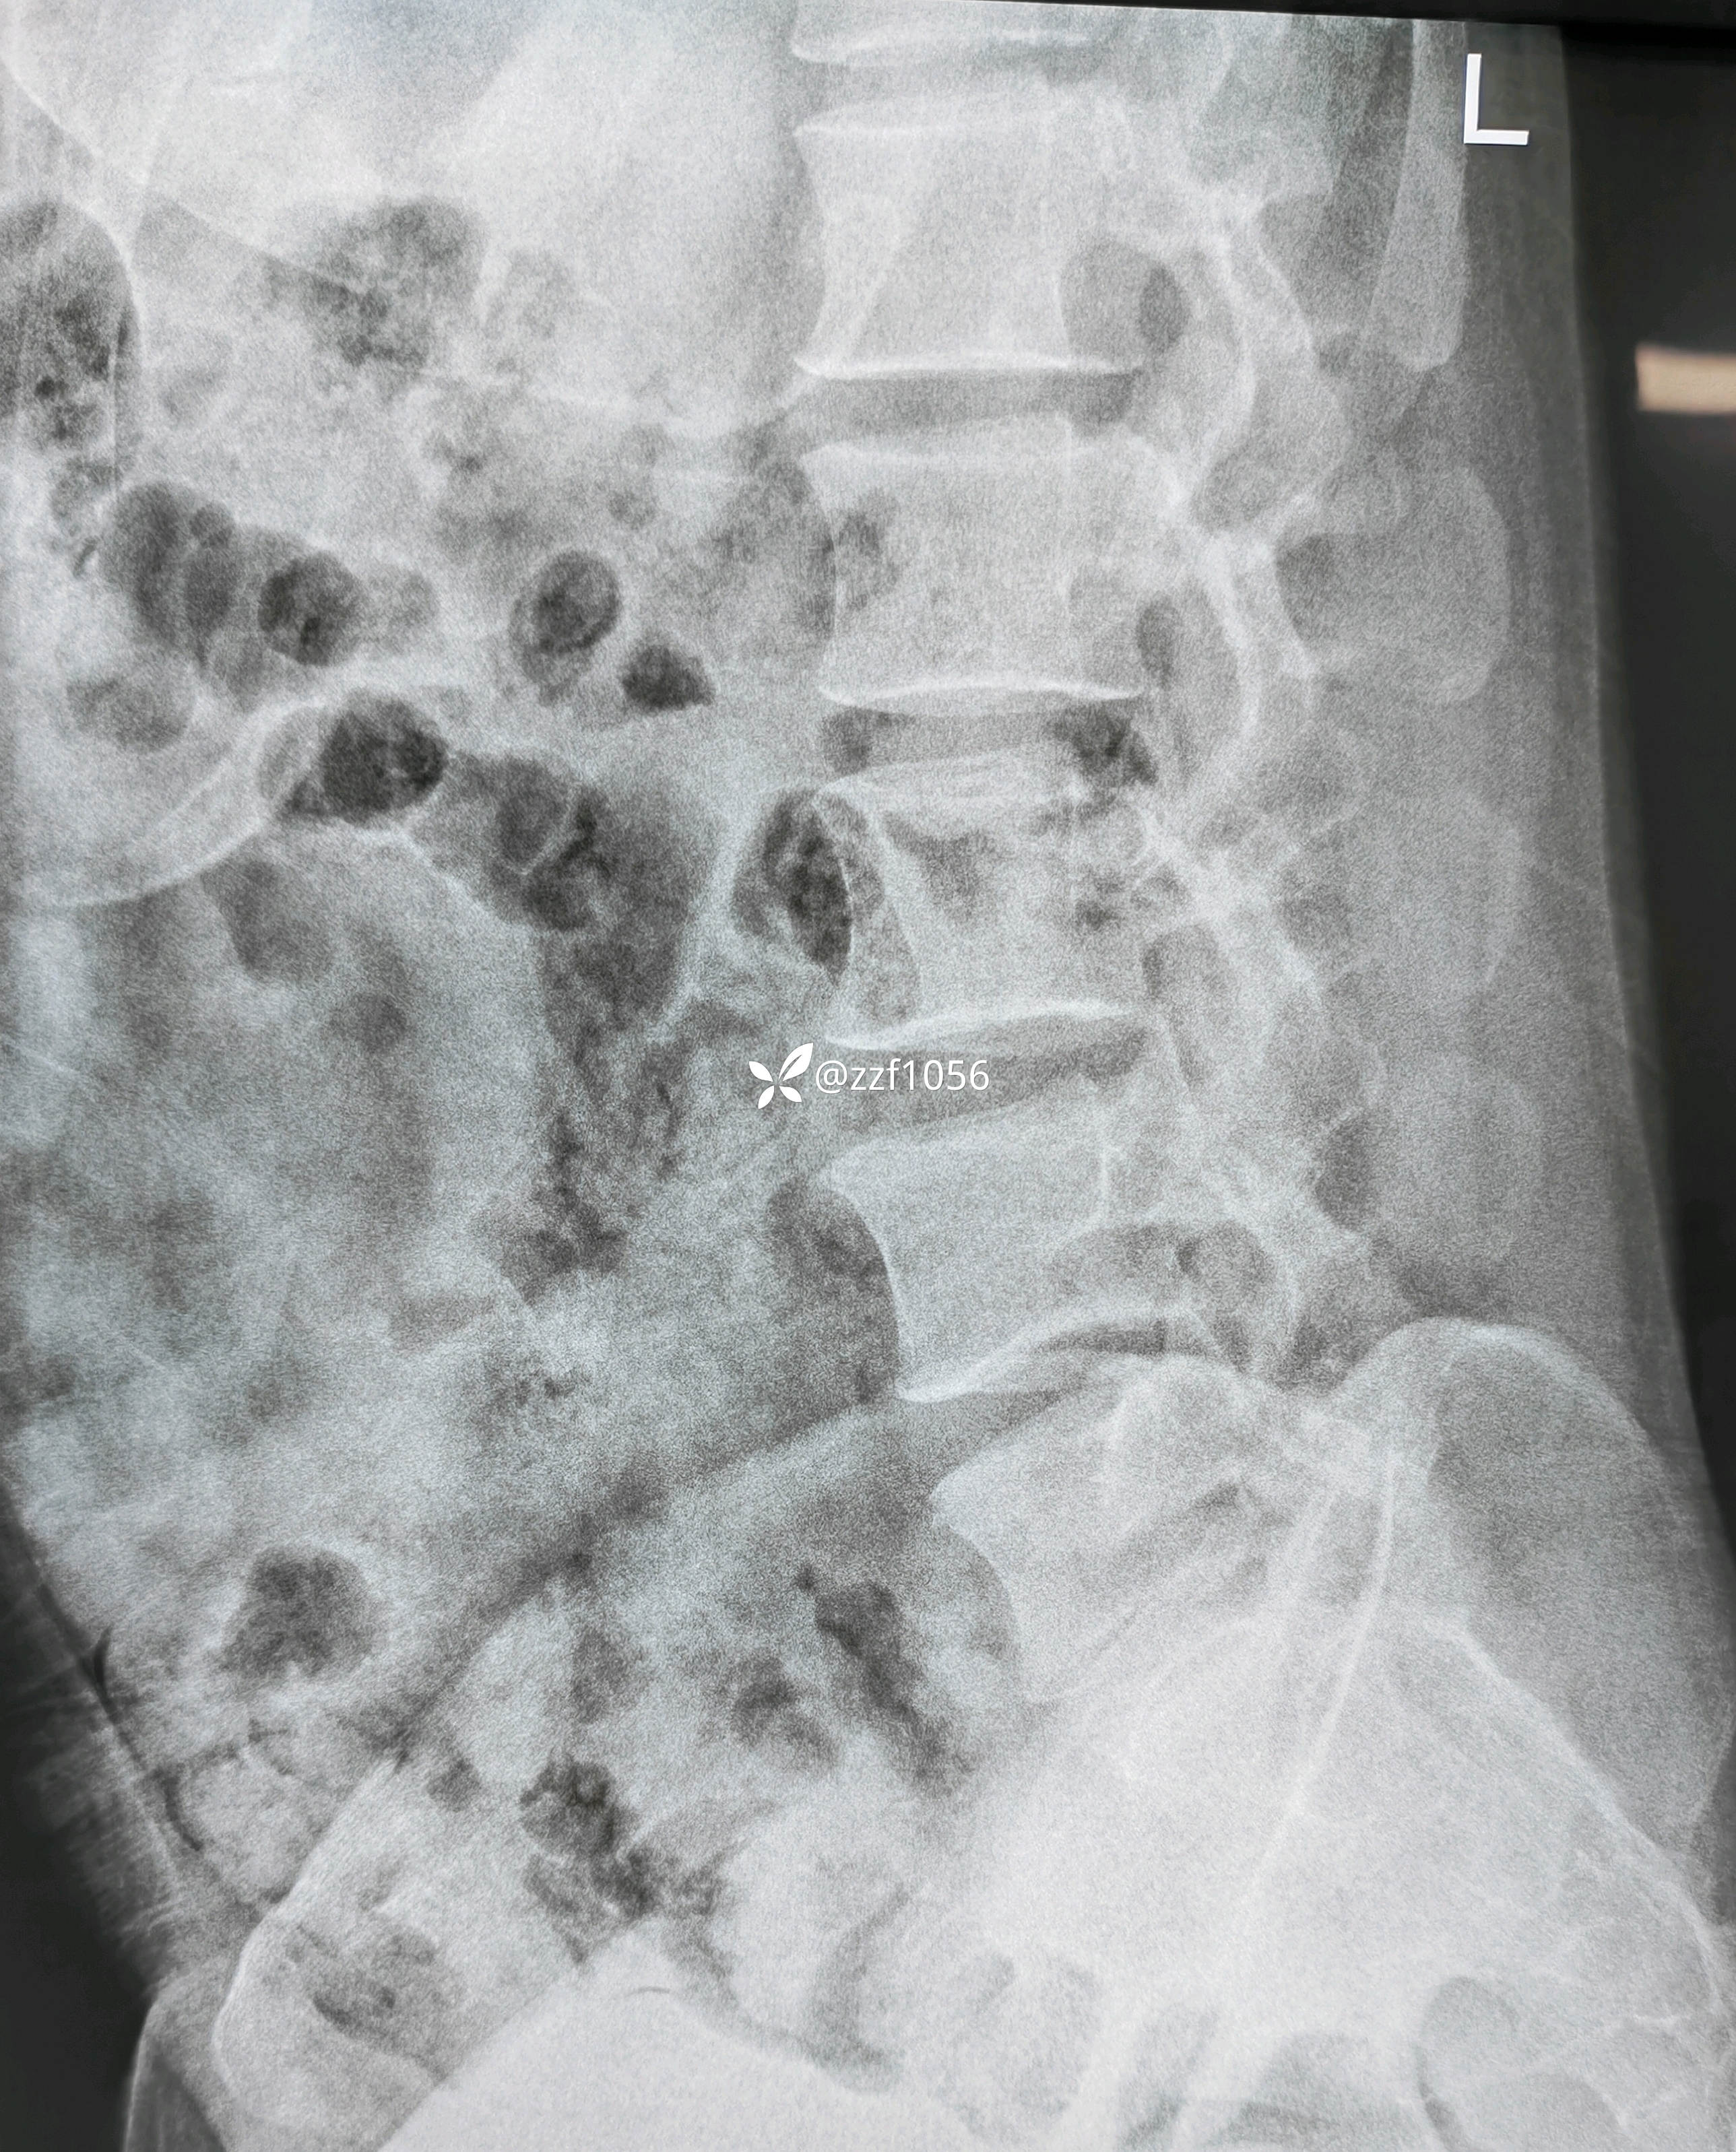

患者男性,39岁,腰痛伴右下肢疼痛麻木不适4个月,加重半个月。

4个月前右膝前叉韧带断裂在我院行重建术,当时腰椎间盘突出症状较轻,一直行保守治疗,半月前LDH症状加重,当地输液半个月无好转,只能被迫俯卧体位,严重影响生活劳作。查体典型右侧L5根性症状,患者同意微创手术,后路ube还是侧路椎间孔镜?

入院诊断:腰椎间盘突出症伴神经根病(L4/5)